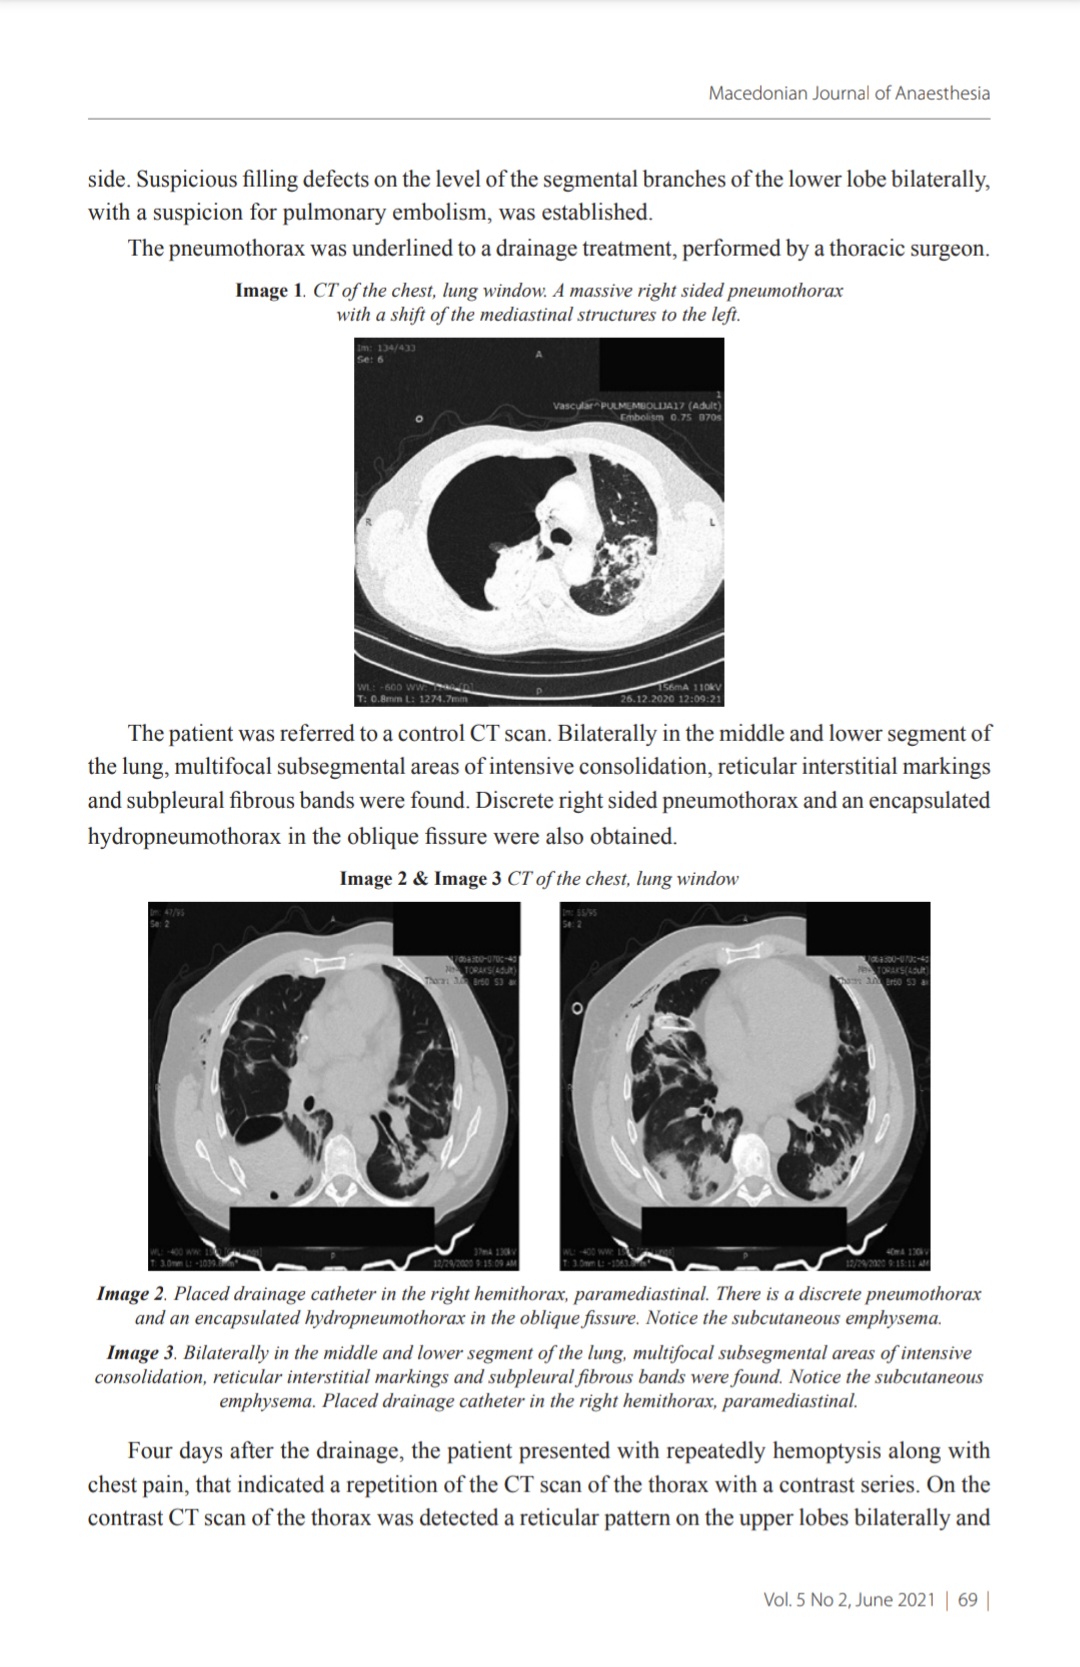

Lung cavitation can occur as a complication in post COVID-19 infection. We present a medical case of a lung cavitation accompanied with aeroliquid formation, as a complication of COVID-19 infection. A 49 year-old man, with active, home-threated COVID-19 infection, PCR confirmed, was primary presented with cough, expectoration of white sputum, high temperature, muscle cramps, malaise.17 days after the diagnosed COVID-19 infection, the patient has requested medical care due to cough and hemoptysis. Computed tomography (CT) scan of the thorax was performed and was detected a massive right sided pneumothorax with a shift of the mediastinal structures to the left side, that underlined to a drainage treatment. The repeatedly hemoptysis along with chest pain, indicated a repetition of the CT scan of the thorax with a contrast series in which was detected a reexpansion of the right lung with an aeroliquid collection in the postero-basal segment of the right lung and a pneumatocele with a ticked wall was detected, in the superior segment of the left lower lobe. With echosonography control, a punctate sample was taken from the aeroliquid formation, with a bloody content, that was sent for microbiological analysis and proofed to be sterile. A thoracic surgeon was consulted, and was indicated surgical treatment.